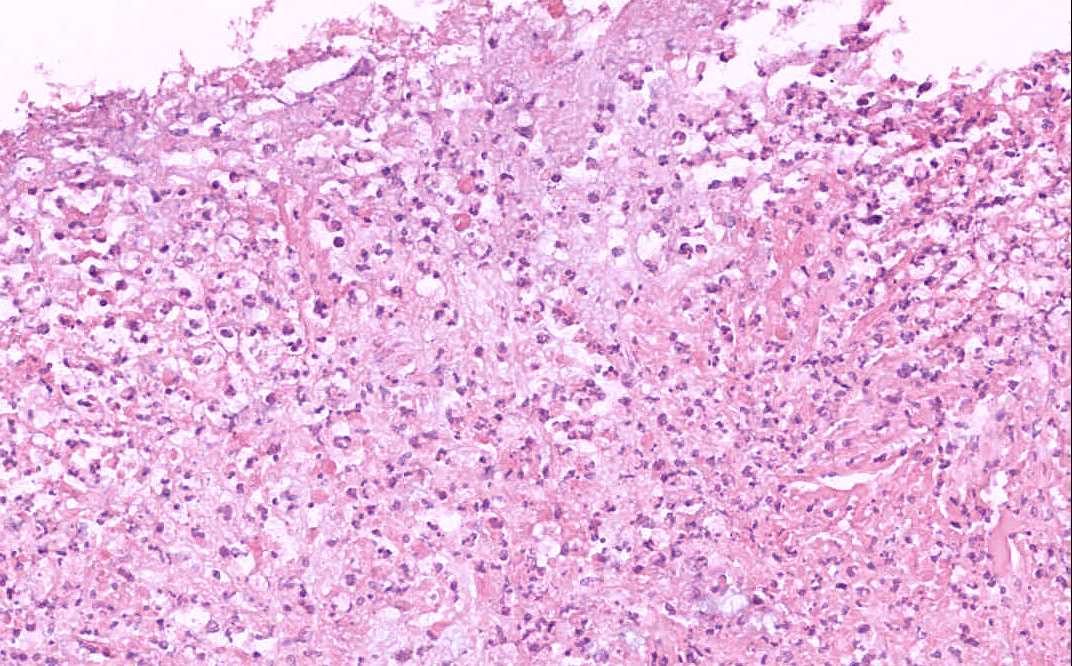

Area 2: Note that the inflammatory necrotic debris has form a pseudomembrane.

• The submucosa (S) is rather edematous and the organization appears loose. The mucosa is rather irregular and is coated by a layer of inflammatory and necrotic substance. There is also patchy necrosis of the superficial aspect os of the mucosa. In the smaller lesions, the affected crypts become dilated and exude an inflammatory and necrotic substance reminiscent of a erupting volcano or mushroom-like structure (Area 1). There is extensive loss of colonic glands due to the necrosis. In the more severely affected areas, the inflammatory and necrotic substance  fuses together to form a pseudomembrane (Area 2). This pseudomembrane extends laterally to overlie adjacent normal appearing mucosa. The exudate is composed largely of karyorrhectic debris and neutrophils. Also the mucin has a tendency to alig with the necrotic debris and neutrophils in an interesting linear arrangement (Area 3).